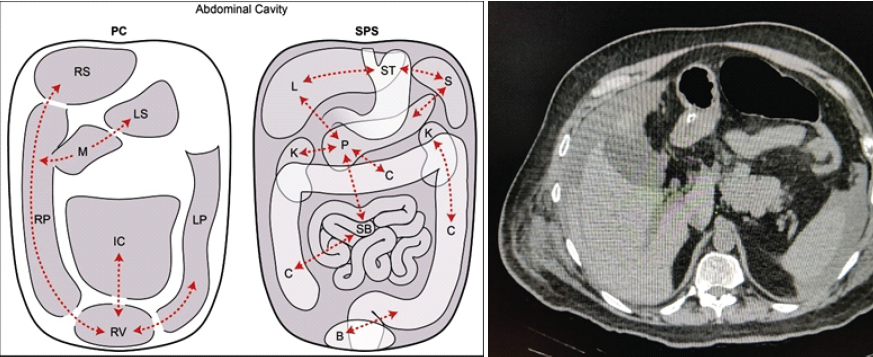

This case presented a unique diagnostic challenge, highlighting a delayed presentation of post-traumatic pancreatitis associated with a SMA pseudoaneurysm in a patient with spine and pelvic fractures. However, the causal linkage between trauma, pancreatitis, and the pseudoaneurysm remains largely inferential, as direct pathophysiological confirmation is not feasible in this setting. Trauma patients, particularly those with multiple injuries, require comprehensive imaging to rule out internal injuries that may not be immediately apparent through physical examination [1]. No comparative group (such as similar polytrauma patients without pancreatic injury) was available, limiting the contextualization of the rarity or clinical course. Pelvic fractures are a common cause of hemorrhagic shock in blunt trauma cases, with mortality rates as high as 30% in patients who present in shock [2,3]. The severity of pelvic and spine fractures correlates with the extent of energy transfer during trauma, requiring careful triage and early intervention to control blood loss [4]. Pancreatic injuries, although uncommon, carry significant risks when they occur in conjunction with other intra-abdominal injuries. The retroperitoneal location of the pancreas makes it difficult to detect injuries early, often resulting in delayed diagnosis and treatment. A high degree of clinical suspicion is necessary to prevent missed pancreatic trauma, especially in polytrauma patients [5]. In cases of pancreatic injury, non-operative management is typically preferred for lower-grade injuries, while higher-grade injuries may require surgical intervention [6,7]. Imaging, particularly CT, plays a critical role in diagnosing pancreatic trauma, as ultrasound findings can be subtle and unreliable. Pseudoaneurysms of the SMA are rare, accounting for only 5.5% of all visceral artery aneurysms. They are often caused by trauma and can lead to life-threatening complications if not identified and treated promptly [8,9]. Angioembolization is the preferred treatment method for SMA pseudoaneurysms due to its lower risk profile and quicker recovery time compared to open surgery [10] (Fig. 5).

Figure 5: The peritoneal cavity (PC) versus the subperitoneal space (SPS). This is a schematic diagram showing the PC on the left and the SPS on the right. Dotted lines show some of these interconnections which allow for disease spread. Abbreviations: IC: Inframesocolic compartment, LP: Left paracolic recess, LS: Lesser sac, M: Morison’s pouch, RP: Right paracolic recess, RS: Right subphrenic space, and RV: Rectovesical space, B: Bladder, C: Colon, K: Kidney, L: Liver, P: Pancreas, S: Spleen, SB: Small bowel, and ST: Stomach [10].